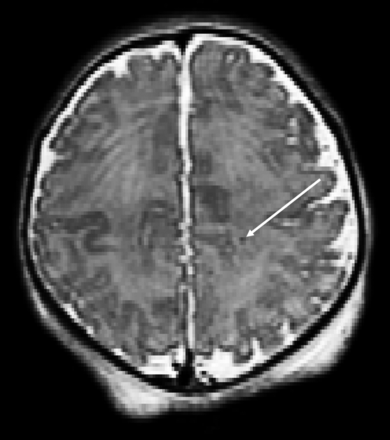

Thirty-two neonates (32.0%) had abnormal findings on conventional preoperative brain MR imaging. Acquired injury was present in 27 (26.2%) neonates. An isolated developmental anomaly (ie, without acquired injury) was detected in 5 neonates, while 5 others presented with both developmental and acquired findings. Hemorrhagic and nonhemorrhagic pWMIs were present in 15 neonates (5 mild, 10 moderate/severe), most commonly observed in the periventricular white matter, the centrum semiovale (Fig 2), and the frontal white matter. NHPI was the second most frequently acquired injury and was detected in 13 neonates. Of these, 7 presented with diffuse abnormal T2 signal prolongation (isolated in 2) in the periventricular white matter and 3 with focal infarctions in the deep gray matter (isolated in 1) (Fig 3). Three neonates presented with cysts: One had an isolated right germinal matrix cyst, 1 had a single cyst in the periventricular white matter, and 1 had multiple cysts in the bilateral frontal white matter.

T2-weighted axial view of a neonate with CHD with punctate white matter injury.